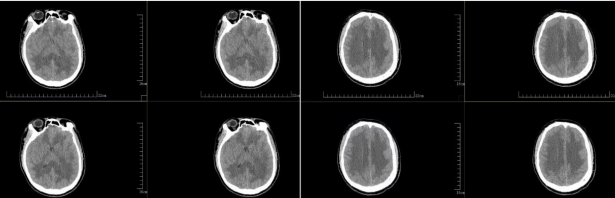

小李脑部CT提示脑水肿